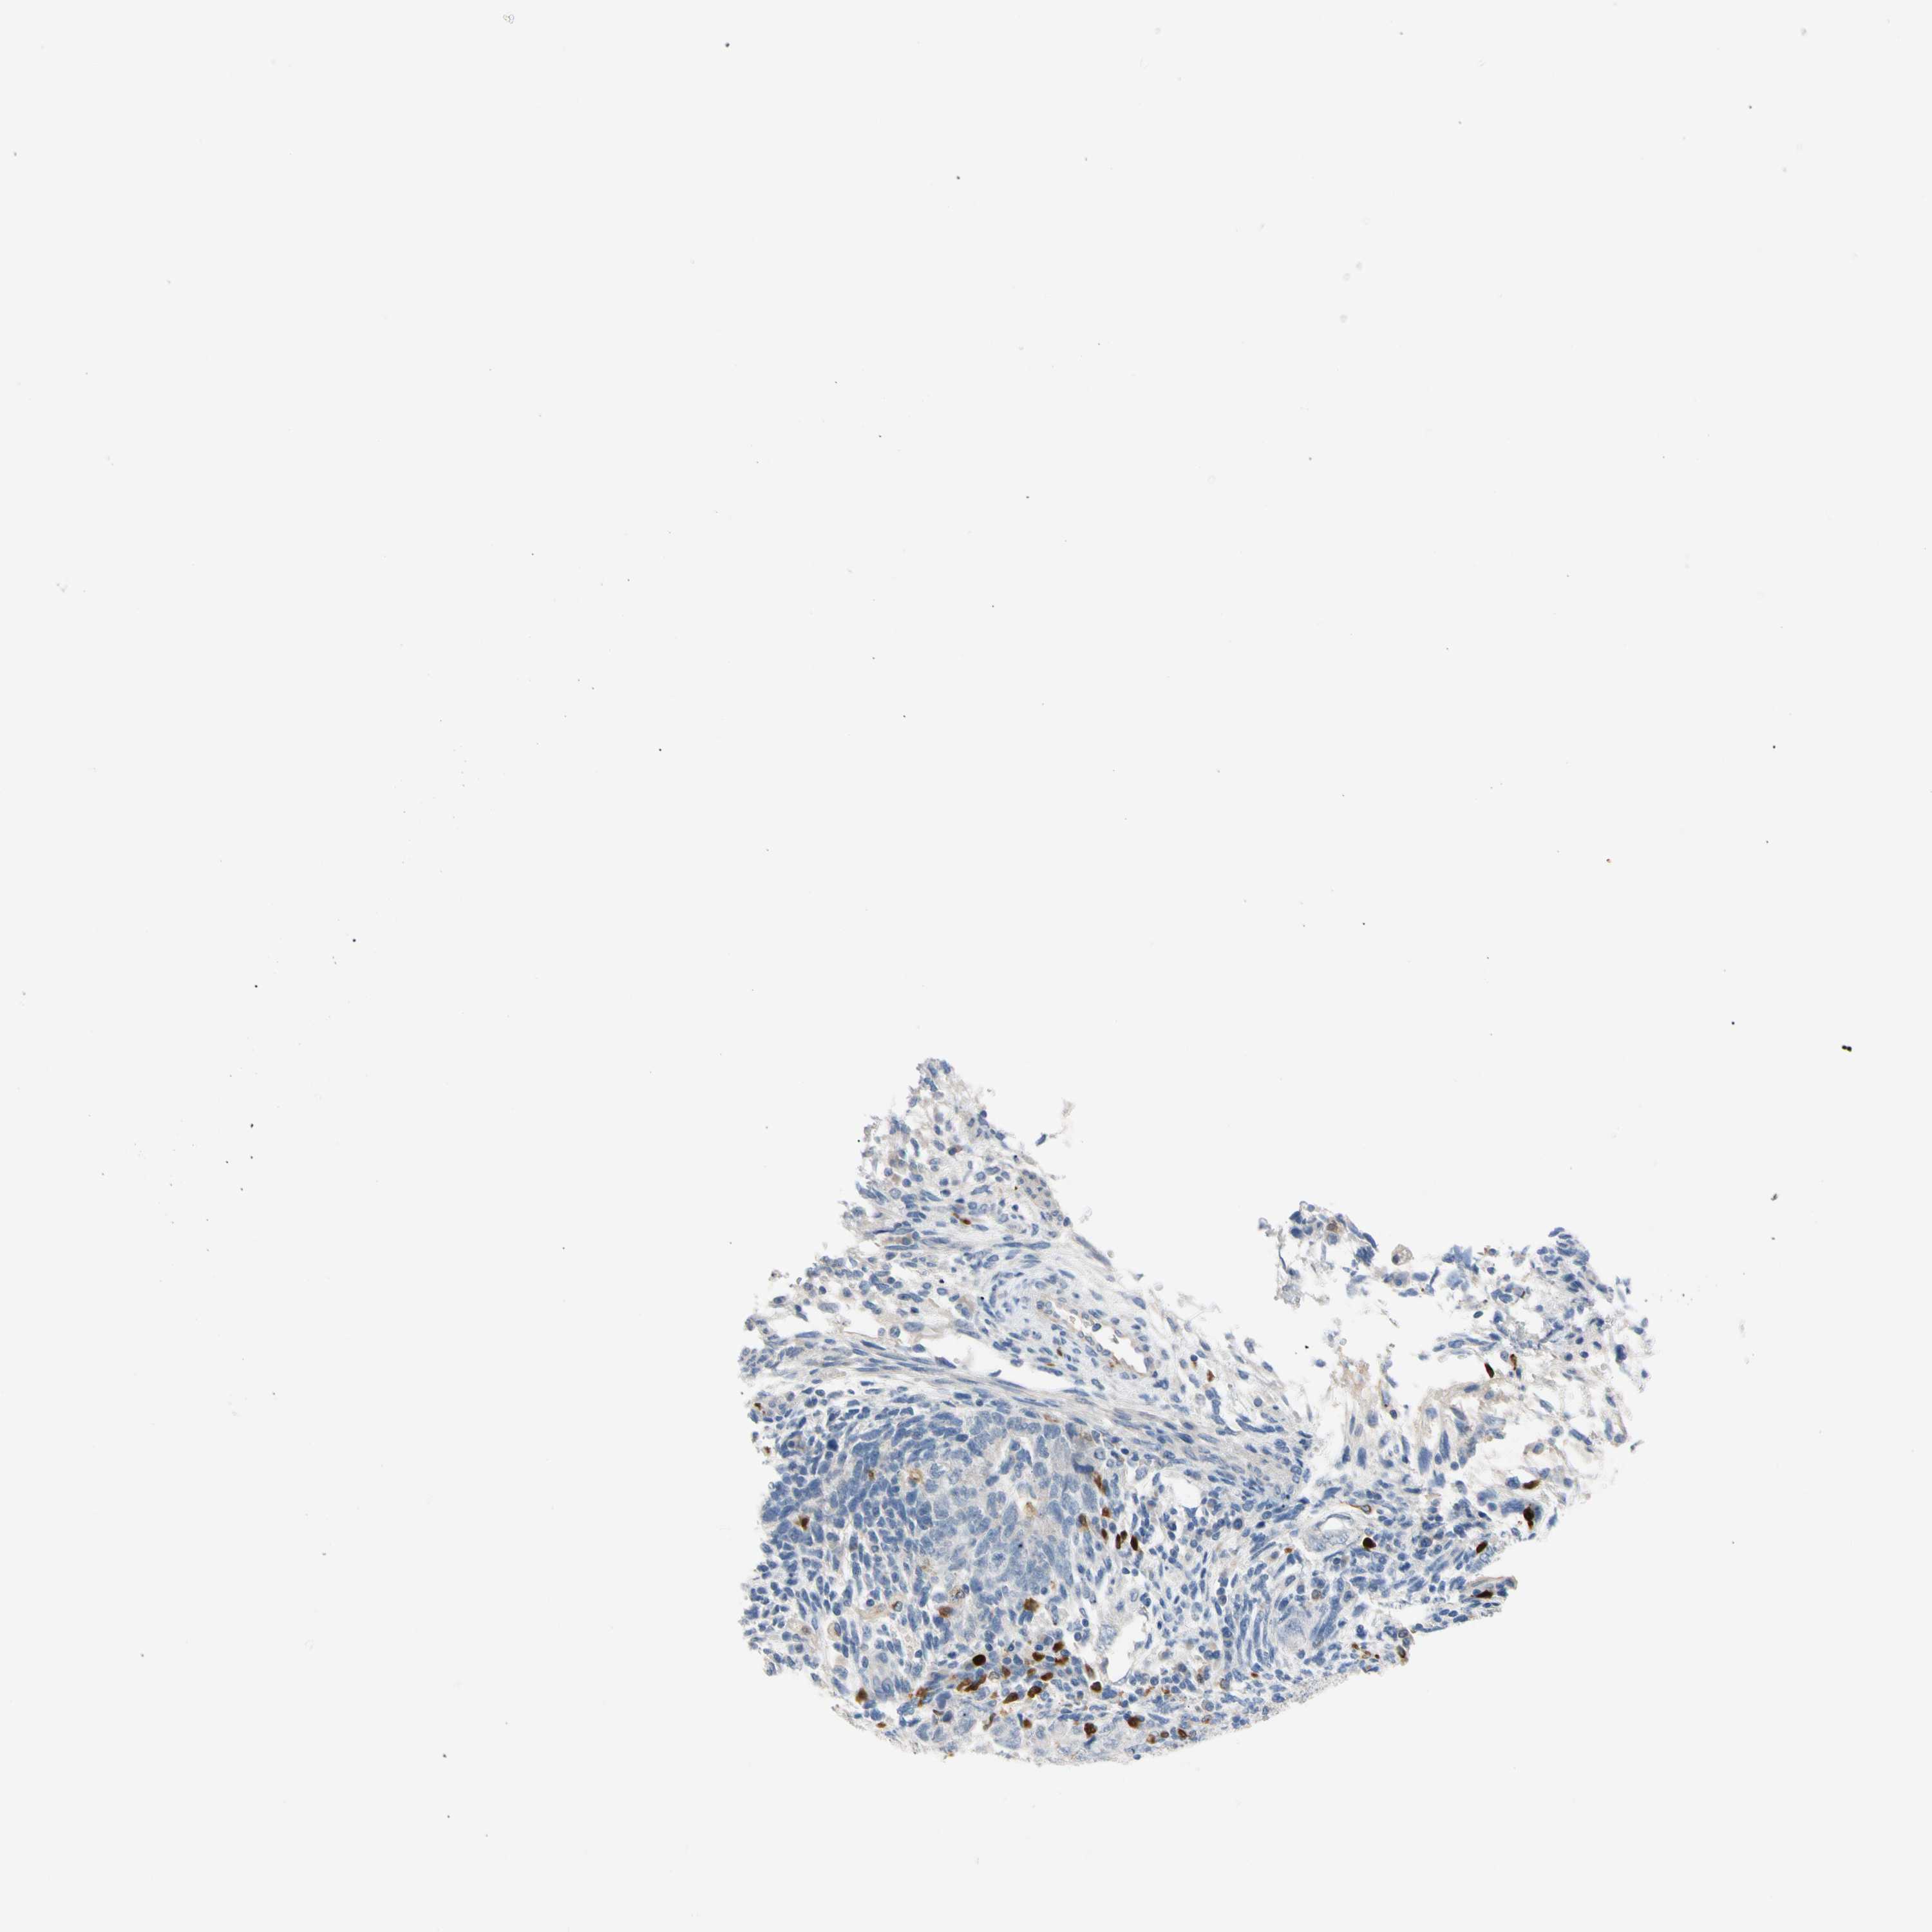

TESTIS CANCER - Protein expressioni

A mouse-over function shows sample information and annotation data. Click on an image to view it in a full screen mode. Samples can be filtered based on level of antibody staining by selecting one or several of the following categories: high, medium, low and not detected. The assay and annotation is described here.

Note that samples used for immunohistochemistry by the Human Protein Atlas do not correspond to samples in the TCGA dataset.

Antibody stainingi

Antibody staining in the annotated cell types in the current human tissue is reported as not detected, low, medium, or high, based on conventional immunohistochemistry profiling in selected tissues. This score is based on the combination of the staining intensity and fraction of stained cells.

Each image is clickable and will lead to virtual microscopy that enables deeper exploration of all samples and also displays staining intensity scores, fraction scores and subcellular localization as well as patient and tissue information for each sample.

Antibody HPA008052

Antibody CAB010277

Carcinoma, Embryonal, NOS

Seminoma, NOS